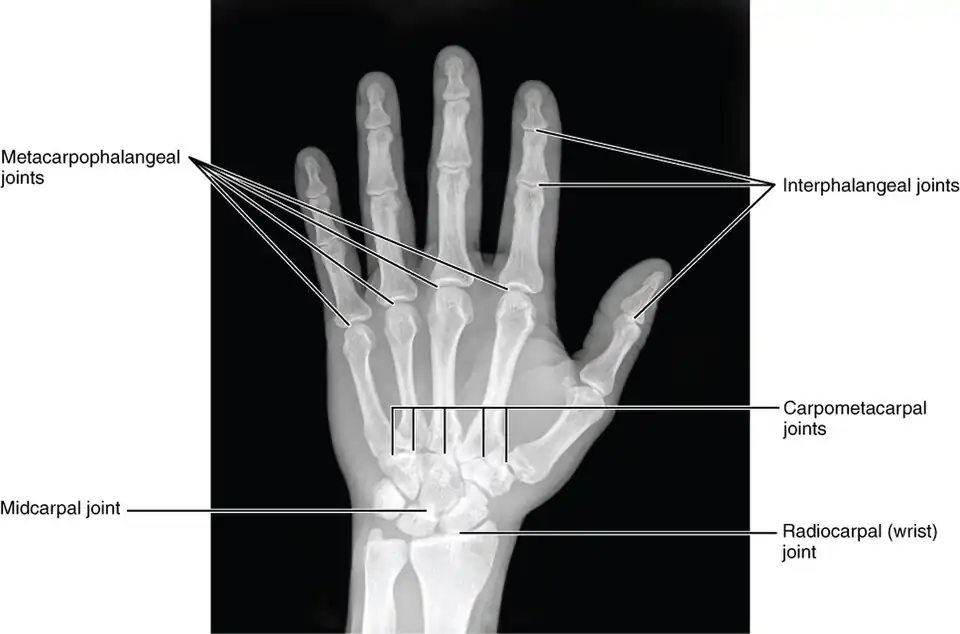

The skeleton of the human hand consists of 27 bones:[10] the eight short carpal bones of the wrist are organized into a proximal row (scaphoid, lunate, triquetral and pisiform) which articulates with the bones of the forearm, and a distal row (trapezium, trapezoid, capitate and hamate), which articulates with the bases of the five metacarpal bones of the hand. The heads of the metacarpals will each in turn articulate with the bases of the proximal phalanx of the fingers and thumb. These articulations with the fingers are the metacarpophalangeal joints known as the knuckles. At the palmar aspect of the first metacarpophalangeal joints are small, almost spherical bones called the sesamoid bones. The fourteen phalanges make up the fingers and thumb, and are numbered I-V (thumb to little finger) when the hand is viewed from an anatomical position (palm up). The four fingers each consist of three phalanx bones: proximal, middle, and distal. The thumb only consists of a proximal and distal phalanx.[11] Together with the phalanges of the fingers and thumb these metacarpal bones form five rays or poly-articulated chains.

The articulations are:

- interphalangeal articulations of hand (the hinge joints between the bones of the digits)

- metacarpophalangeal joints (where the digits meet the palm)

- intercarpal articulations (where the palm meets the wrist)

- wrist (may also be viewed as belonging to the forearm).

Additional images

X-ray showing joints